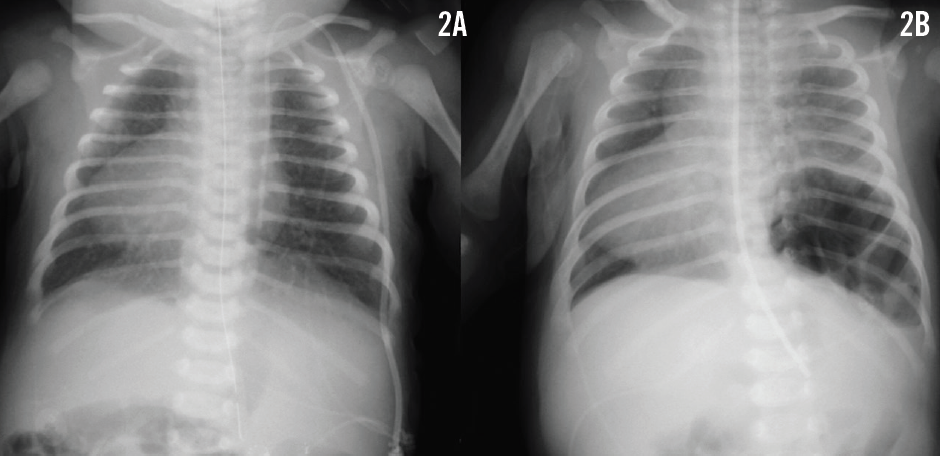

A newborn girl with complex cyanotic congenital heart disease and multiple extracardiac congenital anomalies, including heterotaxy with malrotation, had been sent for a Ladd procedure. Subsequently, the cleft palate was closed. She was also known to have asplenia yet had normal chromosomes. Her heart disease comprised dextrocardia with situs ambiguous viscero-abdominalis and situs inversus thoracalis, a primum atrial septal defect, tricuspid atresia, ventricular inversion, hypoplastic right ventricle, ventricular septal defect, malposed great vessels, and pulmonary stenosis. The results of a chest radiograph at 3 days of age confirmed the dextrocardia and revealed normal lungs (Figure 2A). At 5 weeks of age and long off ventilator support, the girl suddenly developed mild dyspnea. Breath sounds were decreased on the left, pulse oximetry readings were around 80%, and hemodynamic data were stable. A follow-up chest radiograph was obtained (Figure 2B).

The results of the follow-up chest radiograph in patient 2 revealed a left-sided posterolateral delayed congenital diaphragmatic hernia (Figure 2B). The hernia was repaired along with a Nissen fundoplication procedure and a gastrostomy-tube placement. The patient subsequently required additional surgeries for gastrocutaneous fistula, pneumoperitoneum, and peritonitis. At 6 months of age, a left-sided bidirectional Glenn anastomosis was placed uneventfully. At 3 years of age, the Fontan circulation was completed. Both patients are now 5 years of age and are doing well.